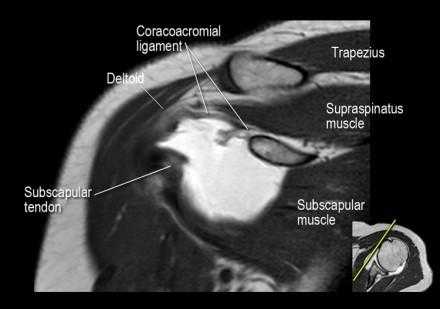

Нормальная корональная анатомия плечевого сустава и контрольный список

- обратите внимание на клювоакромиальную связку (coracoacromial ligament).

- поищите скопление жидкости в подакромиальной сумке и повреждение сухожидия надостной мышцы